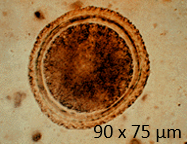

What type of egg is shown?

Smooth egg shell (Toxascaris leonina)

Rough pitted egg shell (Toxocara canis/cati)

Strongyle egg (Hookworm, either Ancylostoma or Uncinaria)

Bipolar plugs (Trichuris egg)